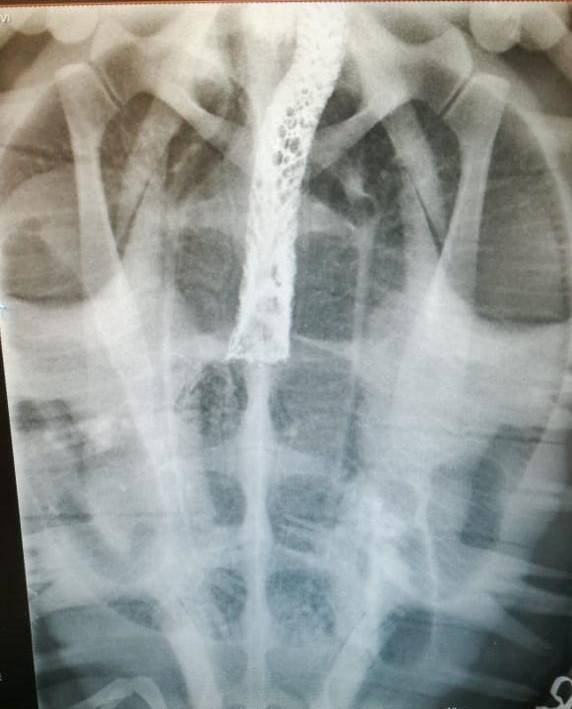

Suspecting a possible lung infection or pneumonia, we started with antibiotics and supportive medication. Over the next couple of days, we noticed that the turtle was becoming weaker. Five days after its arrival, a barium study was done to investigate if the turtle possibly had a blockage. A Barium study takes place over a couple of days, and when X-rayed four days later, we found that the Barium had not moved as one would expect. We were able to confirm that the turtle indeed had some kind of obstruction in its oesophagus.

The Barium study clearly showed an obstruction Photo: Talitha Noble